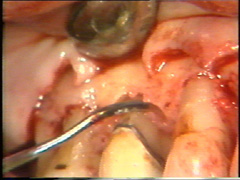

Las superficies de la raíz se limpian

(raspado y alisado radicular) cuidadosamente y el tejido de granulación en los

defectos óseos (cráter) es eliminado. En la superficie bucal del segundo premolar hay

un cráter óseo y cálculo en la supericies dental adyacente.

El cálculo del segundo premolar

está unido firmemente a la superficie dental y es un proceso tedioso el

quitarlo.

En la superficie

palatina del central, hay un defecto grande en la superficie de la raíz. Probablemente

sea una fractura que ocurrió en relación con el accidente. El tejido de

granulación se ha formado en el defecto que se limpia completamente. Postoperatoriamente es necesario poner

apicalmente el colgajo en relación con el defecto de la raíz para crear una condición higiénica manejable